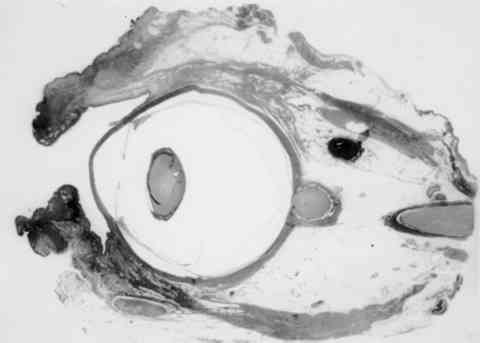

Figura 5

PIEZA DE EXENTERACIÓN ORBITARIA (MAGNIFICACIÓN ORIGINAL X 2,5).